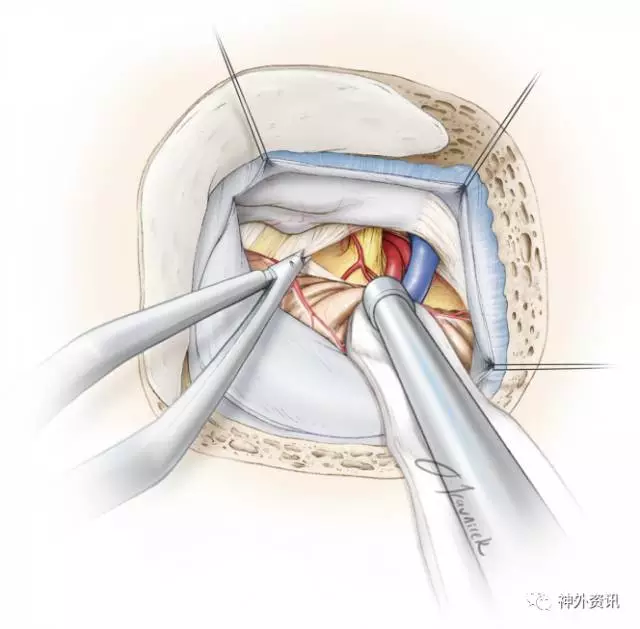

图11. 将切碎的Teflon置于神经和责任血管之间:通常是游离动脉,并在REZ区沿神经平行置入Teflon,以防止血管压迫REZ区及整个三叉神经脑池段。

笔者用撕碎的Teflon棉团来防止神经与血管的接触。考虑到植入物术后移位的风险,应避免使用未撕碎的Teflon棉片。Teflon棉团置入后沿着神经向前推动,这种方法让这些小片植入物符合动脉的形状,从而尽可能降低Teflon棉团迟发性移位的分险。

图12. 笔者特意在三叉神经肩部及腋内侧塞入一块teflon棉垫,防止血管与REZ区或脑干之间的任何接触。